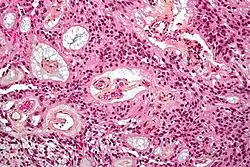

| Micrograph of an ependymoma. H&E stain. | |

Ependymomas are composed of cells with regular, round to oval nuclei. There is a variably dense fibrillary background. Tumor cells may form gland-like round or elongated structures that resemble the embryologic ependymal canal, with long, delicate processes extending into the lumen; more frequently present are perivascular pseudorosettes in which tumor cells are arranged around vessels with an intervening zone consisting of thin ependymal processes directed toward the wall of the vessel.[5]